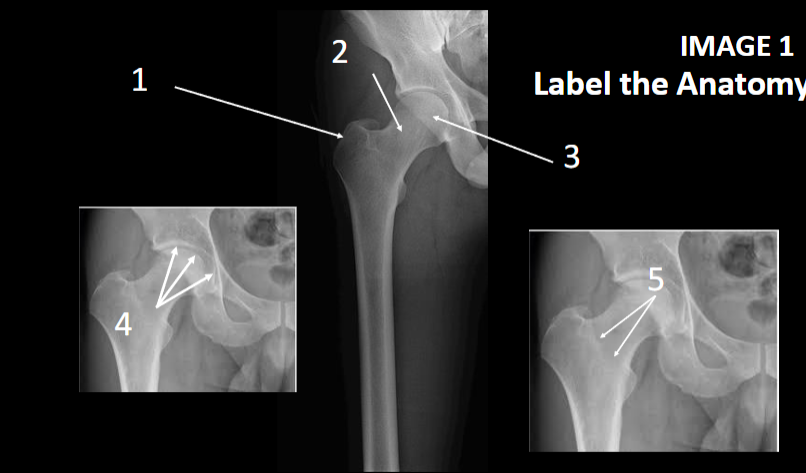

1

greater trochanter

2

femoral neck

3

Femoral head

4

acetabulum

5

intertrochanter Crest